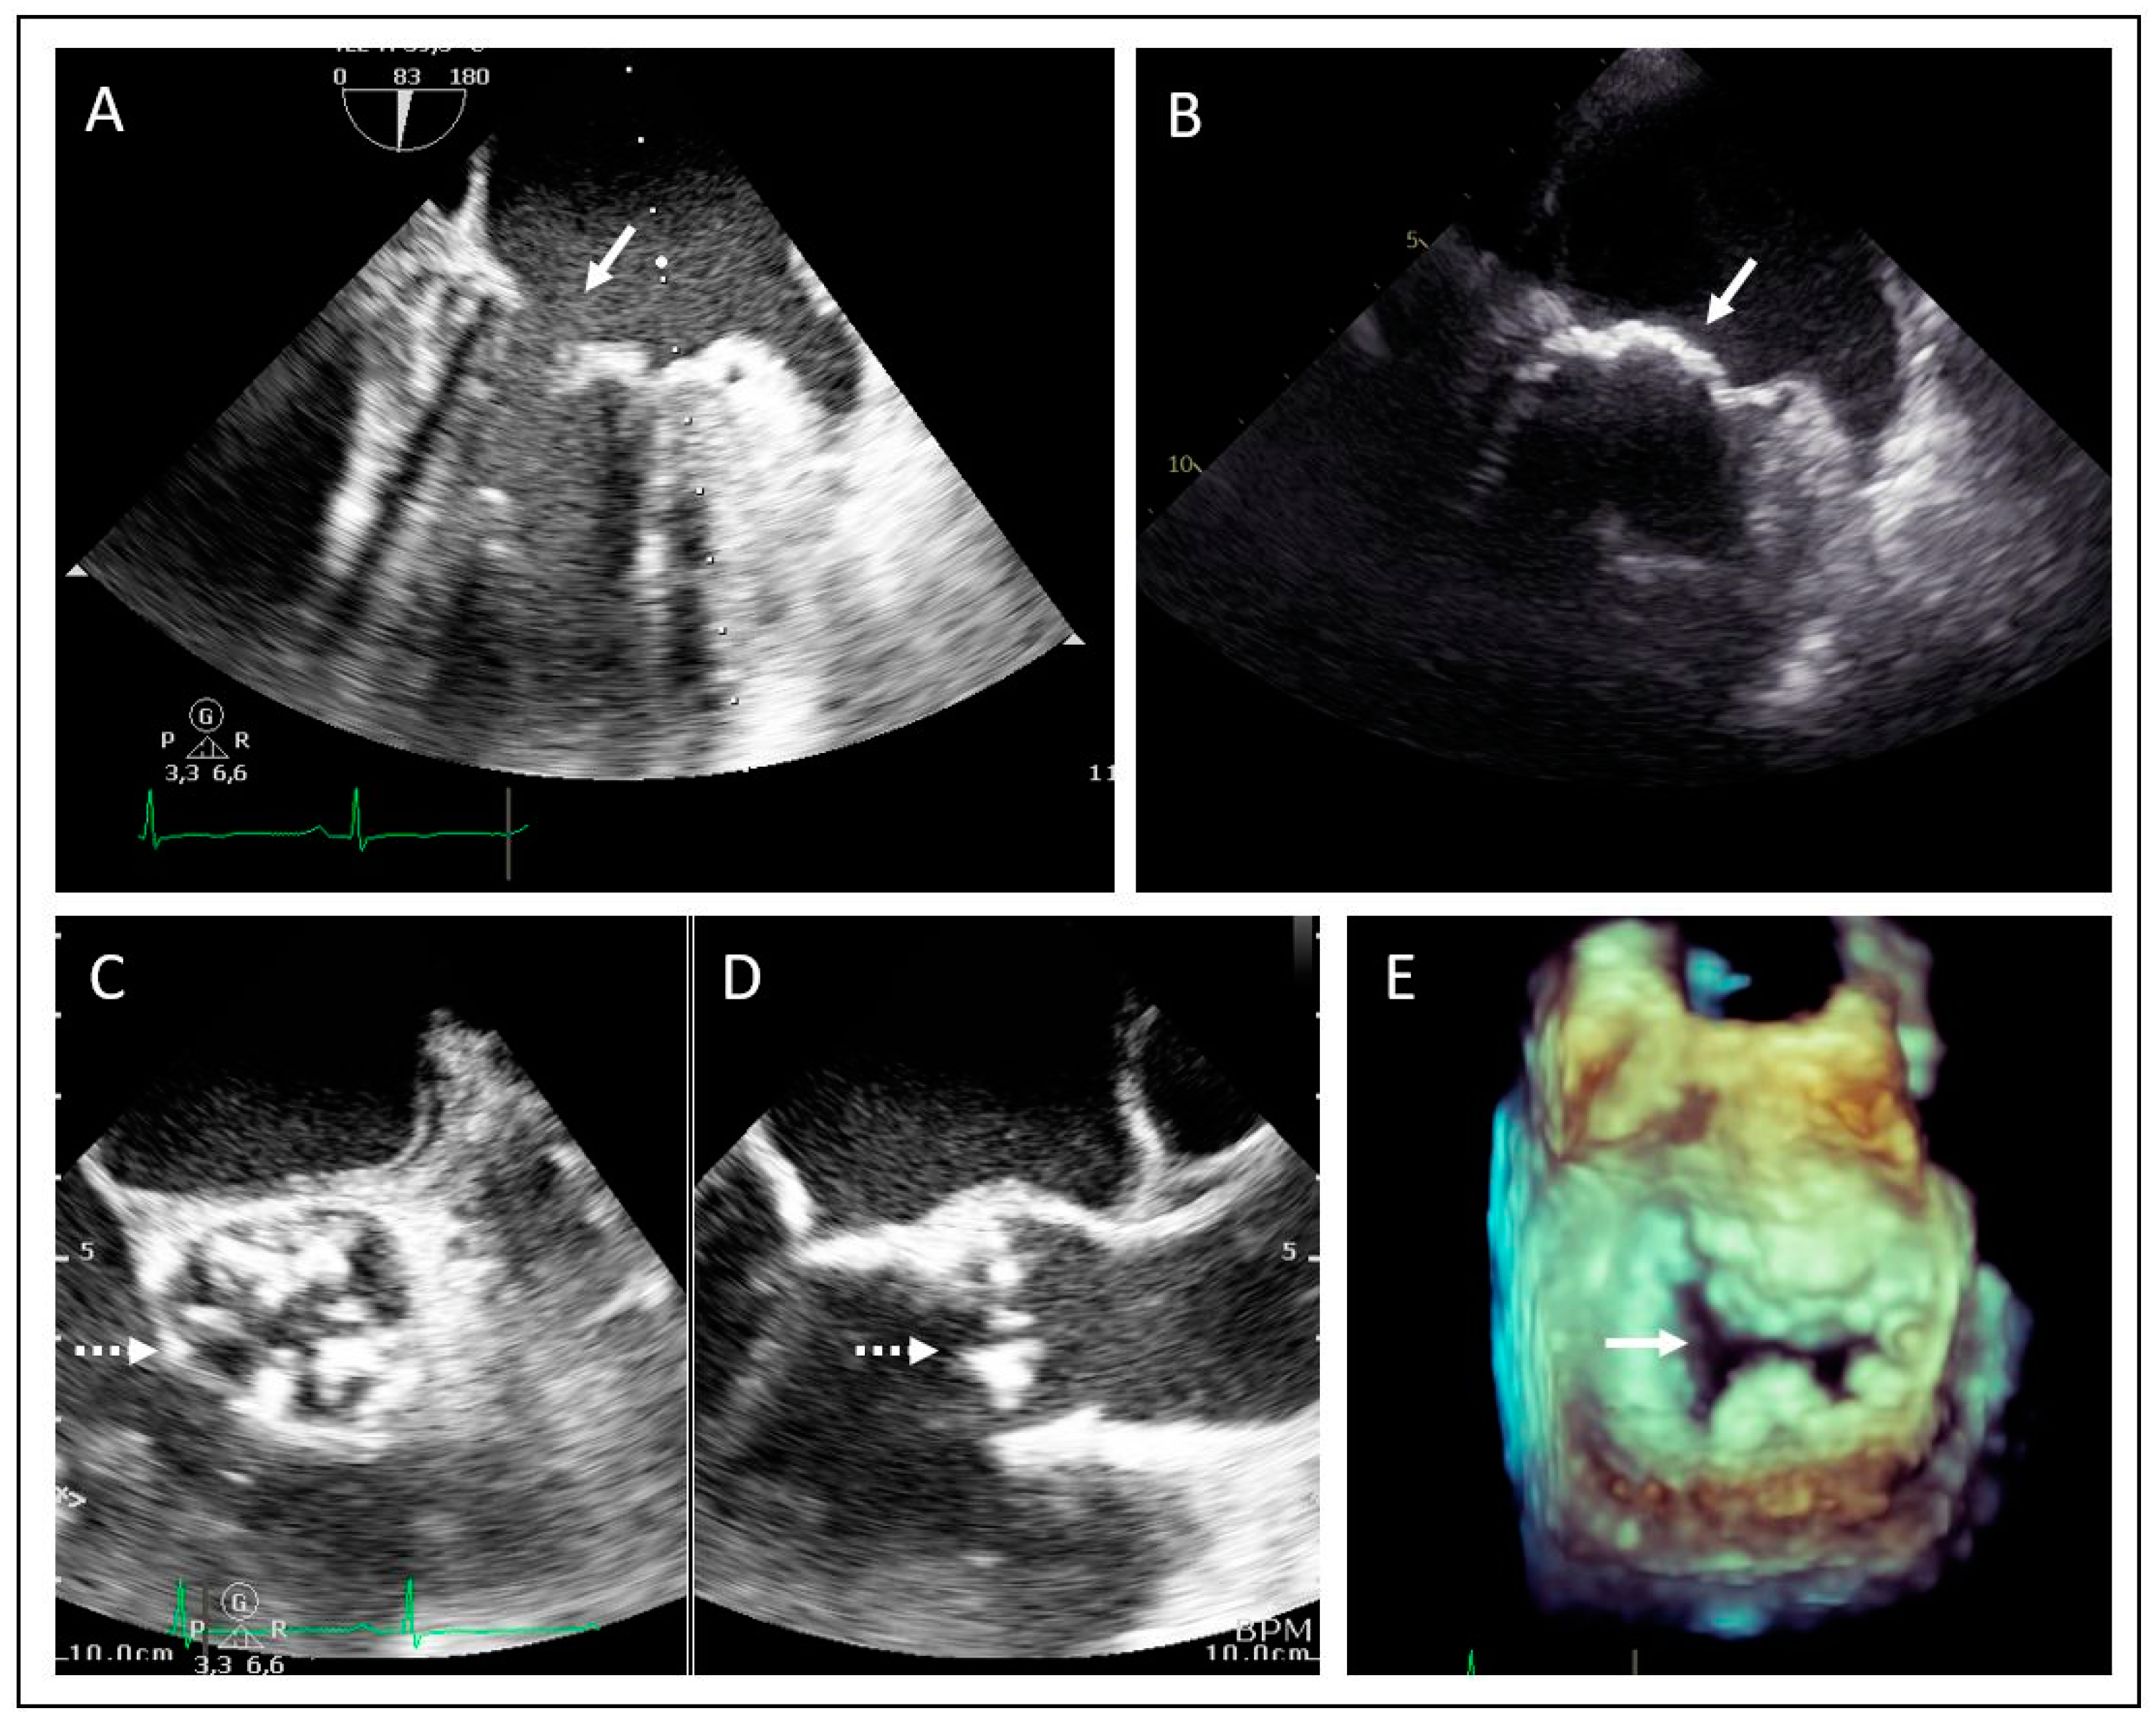

2. Case Presentations

2.1. Family 1

2.2. Family 2